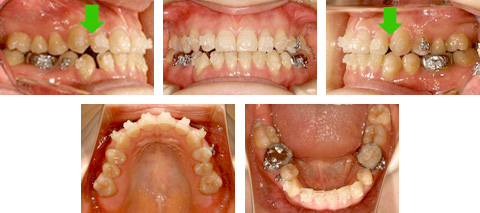

裁断しています「歯列矯正治療の失敗と再治療 : 臨床現場からのレポート」菅原 準二定価: ¥ 17000#菅原準二 #菅原_準二 #本 #自然/医療・薬学・健康